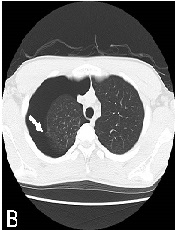

A Combination of Hodgkin's Lymphoma and Tuberculosis occurred with Bilateral Malignant Pleural Effusions

Daniel Valchev*, Mitko Mitev, Evelin Obretenov, Dimitar Kostadinov, Danail Petrov